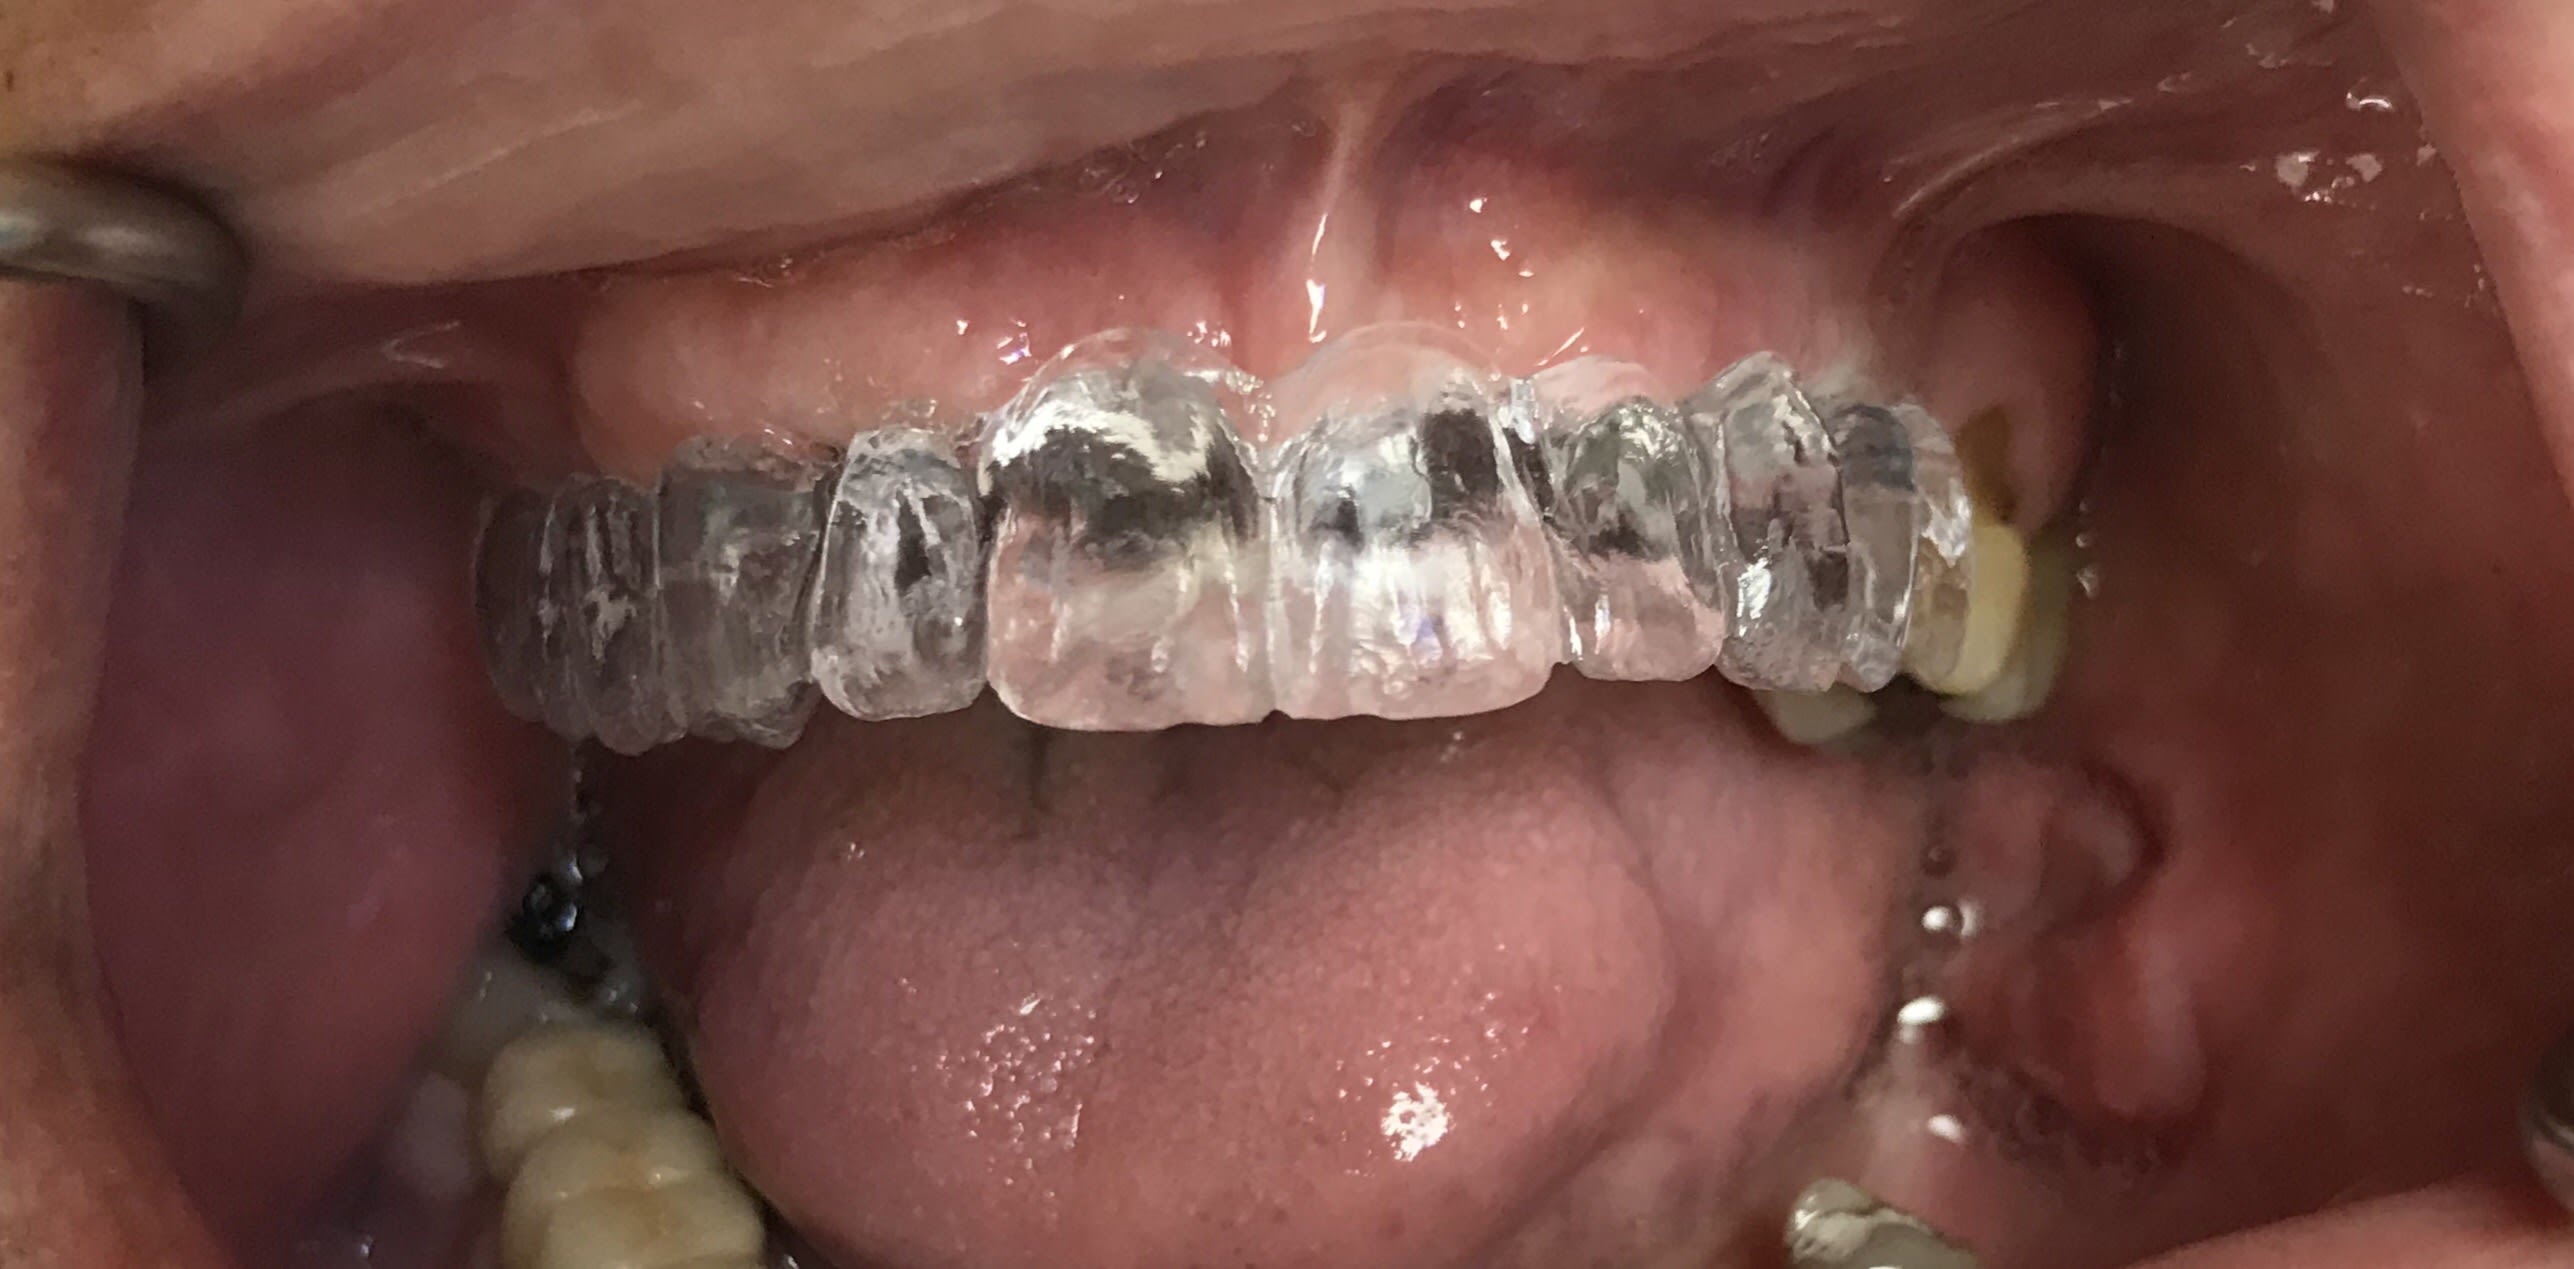

Oh p...n même pas de digue, ça va chauffer pour moi, mais le moteur y sait tout faire

Je sais pas pourquoi tu reprends d aussi belles endos... Ça me paraît conforme aux exigences de qualité rac0...

Je ne vois pas trop l’intérêt de cette radio de cas simples ni de la ramener sur le travail sans champ qui plus est par les temps qui courent.

Tu penses que l absence de champs opératoire ,dans ce cas, empêchera la cicatrisation de la lésion ?